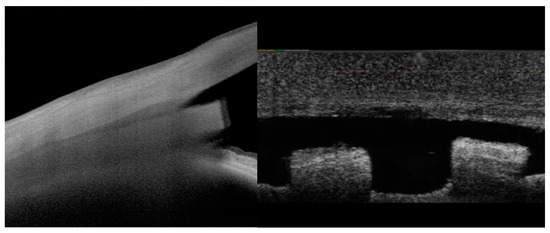

When used for endoscleral or episcleral reinforcement, the allograft implant is homologous and has biological and biomechanical properties similar to those of the native surrounding tissue (Figure 1). This is important regarding the risk of implant fibrosis, as sterilized allograft scleral tissue has one of the lowest indices of material stiffness mismatch when implanted adjacent to the scleral surface, thereby reducing the potential for fibrosis and macrophage activation as compared to stiffer implantable non-biologic materials such as nitinol or polyimide [19,20].

Figure 1.

Scleral allograft bio-reinforcement in the eye demonstrates high homogeneity with native tissues on OCT imaging. High-resolution longitudinal OCT imaging using Anterion® OCT and transverse OCT imaging of the allograft at the endoscleral (supraciliary) interface.